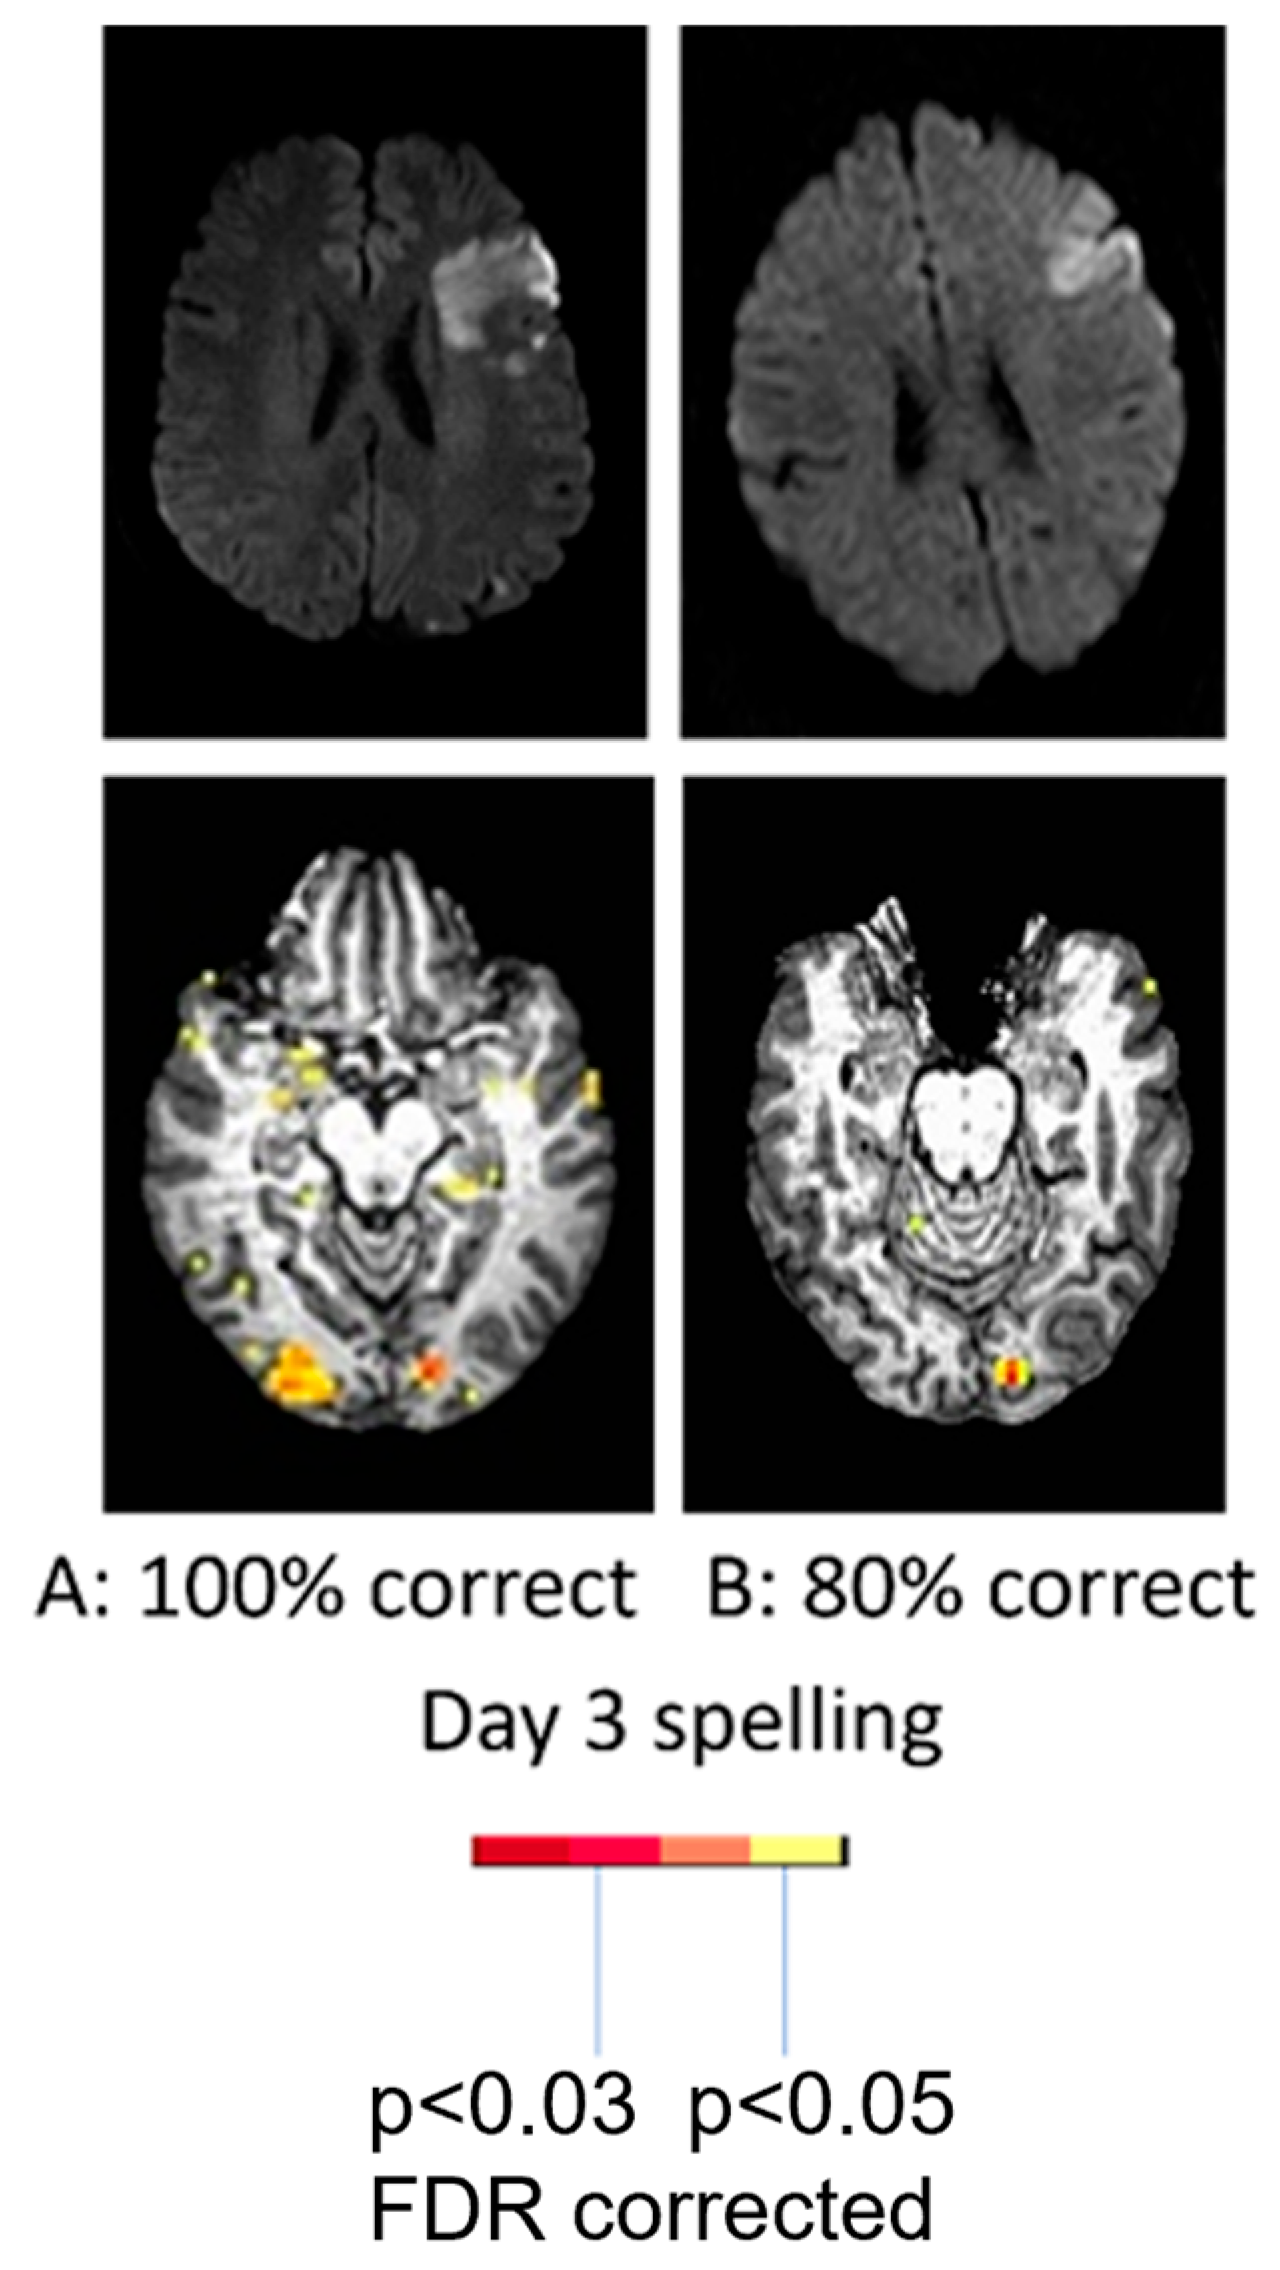

With regard to the effect of accuracy of performance, two women of similar ages with very similar infarcts involving left posterior inferior frontal cortex (“Broca’s area”), showed quite different patterns of activation during a spelling task (identifying the missing letter in a word vs. identifying the letter with a different case in a word) at Day 3. While the participant with 100% accuracy showed bilateral (right more than left) activation in areas similar to controls, the participant with 80% accuracy showed only left hemisphere activation as shown in Figure 2. These data raise doubts that right hemisphere homologous activation is detrimental, since it was associated with flawless performance [26,29].

Figure 2.

(Top) Diffusion-weighted images showing acute infarct in similar areas of left IFG. (Lower panel) Bilateral occipital activation and temporal activation during picture naming in the woman with accurate naming (left); only left occipital activation during picture naming in the woman with impaired naming (right).